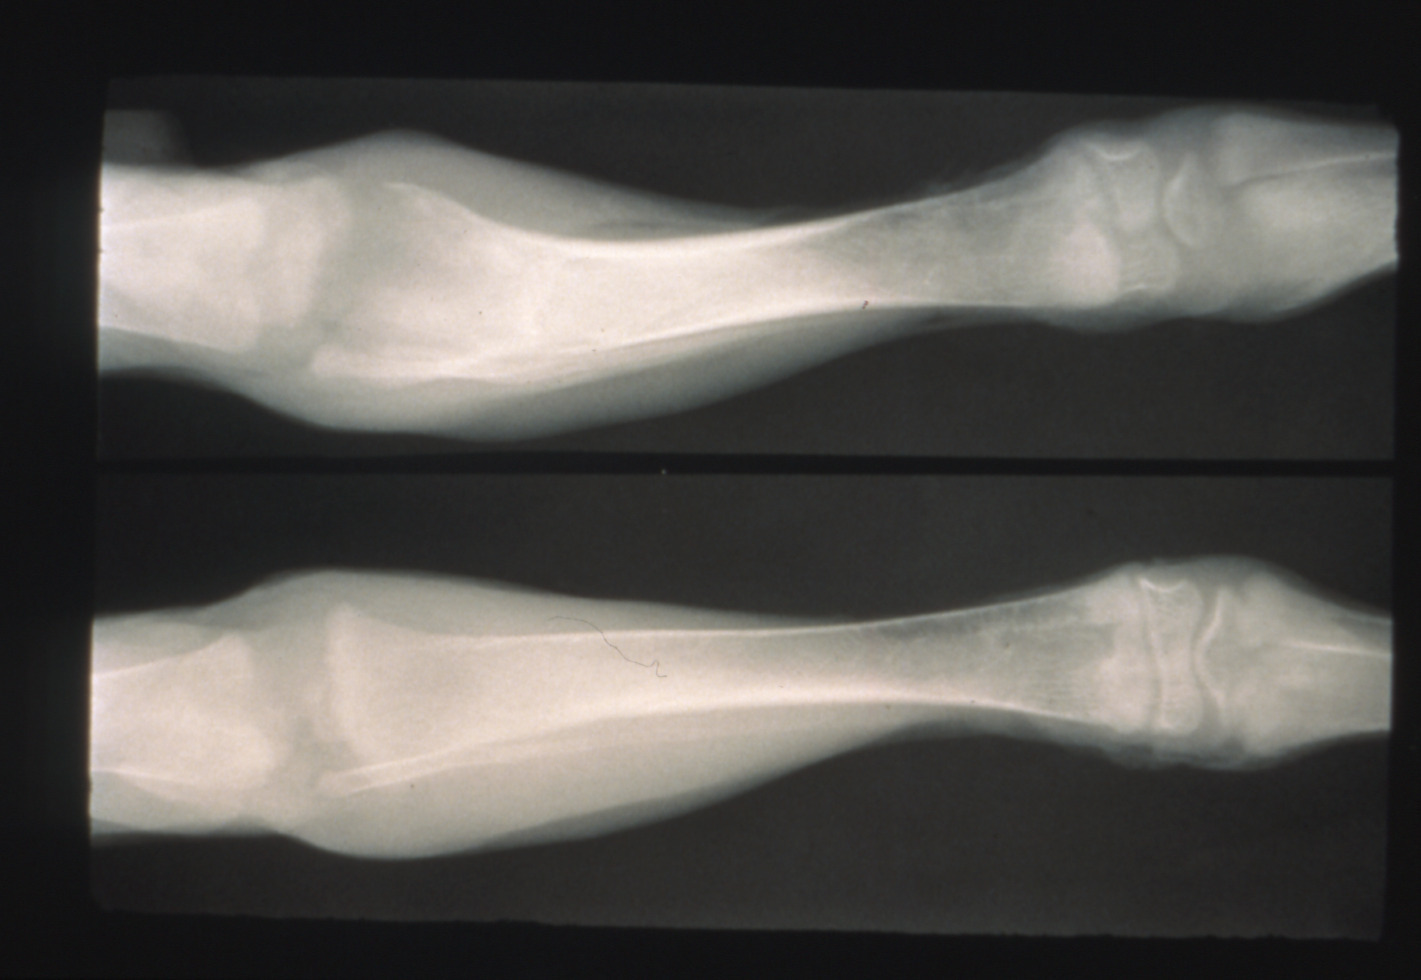

Tibial dyschondroplasia in domestic poultry (slide study set no. 6) Item Info

Tibial dyschondroplasia in domestic poultry (slide study set no. 6)

Avian medicine Poultry--Diseases Tibia

Slide Study Set #6, Tibial Dyschondroplasia, 2 sets (includes 34 color slides), 1975